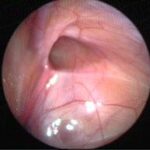

Can this operation done by laparoscopy?

Operation in hernia involves closing of the open passage through which the testis has come down. This can be done from outside as in open surgery or from inside by laparoscopy. If your child has got a hernia on one side, there is a 15 – 25 % chance that he / she may develop a hernia on the opposite side at a later date. With the help of laparoscopy we are able to look at the opposite side to see if the passage is open on that side as well. This can be closed at the same sitting if you wish to. Recovery from surgery, timing of surgery and discharge from hospital are the similar for open surgery and laparoscopic surgery.